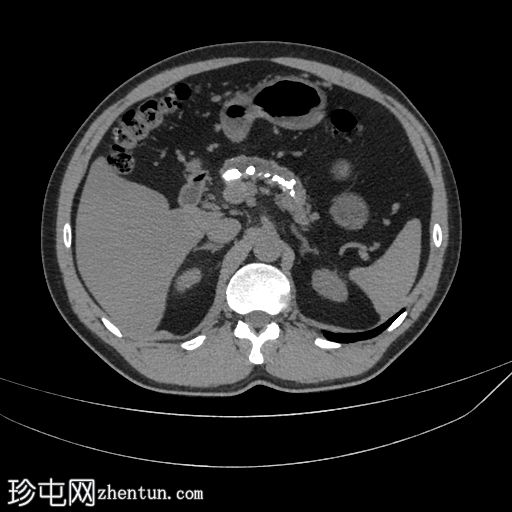

轴位

平扫

胰腺萎缩、粗大钙化及主胰管扩张

无急性胰腺炎征象

肝脂肪变性

左侧结肠憩室

主胰管扩张、胰腺萎缩和钙化是慢性胰腺炎诊断的关键。该患者有反复发作的急性胰腺炎病史。